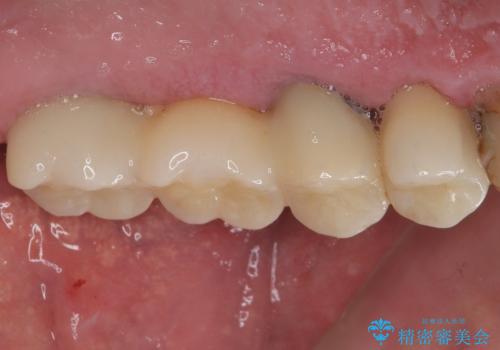

割れてしまった奥歯 抜歯即時埋入インプラントによる短期間治療

いずれの歯も抜歯が必要な状態であり、抜歯即時埋入によるインプラント治療を行うこととしました。

術後にインプラントの安定値を測定し、十分な値が達成された後、速やかにセラミッククラウンにて補綴治療を行うこととしました。